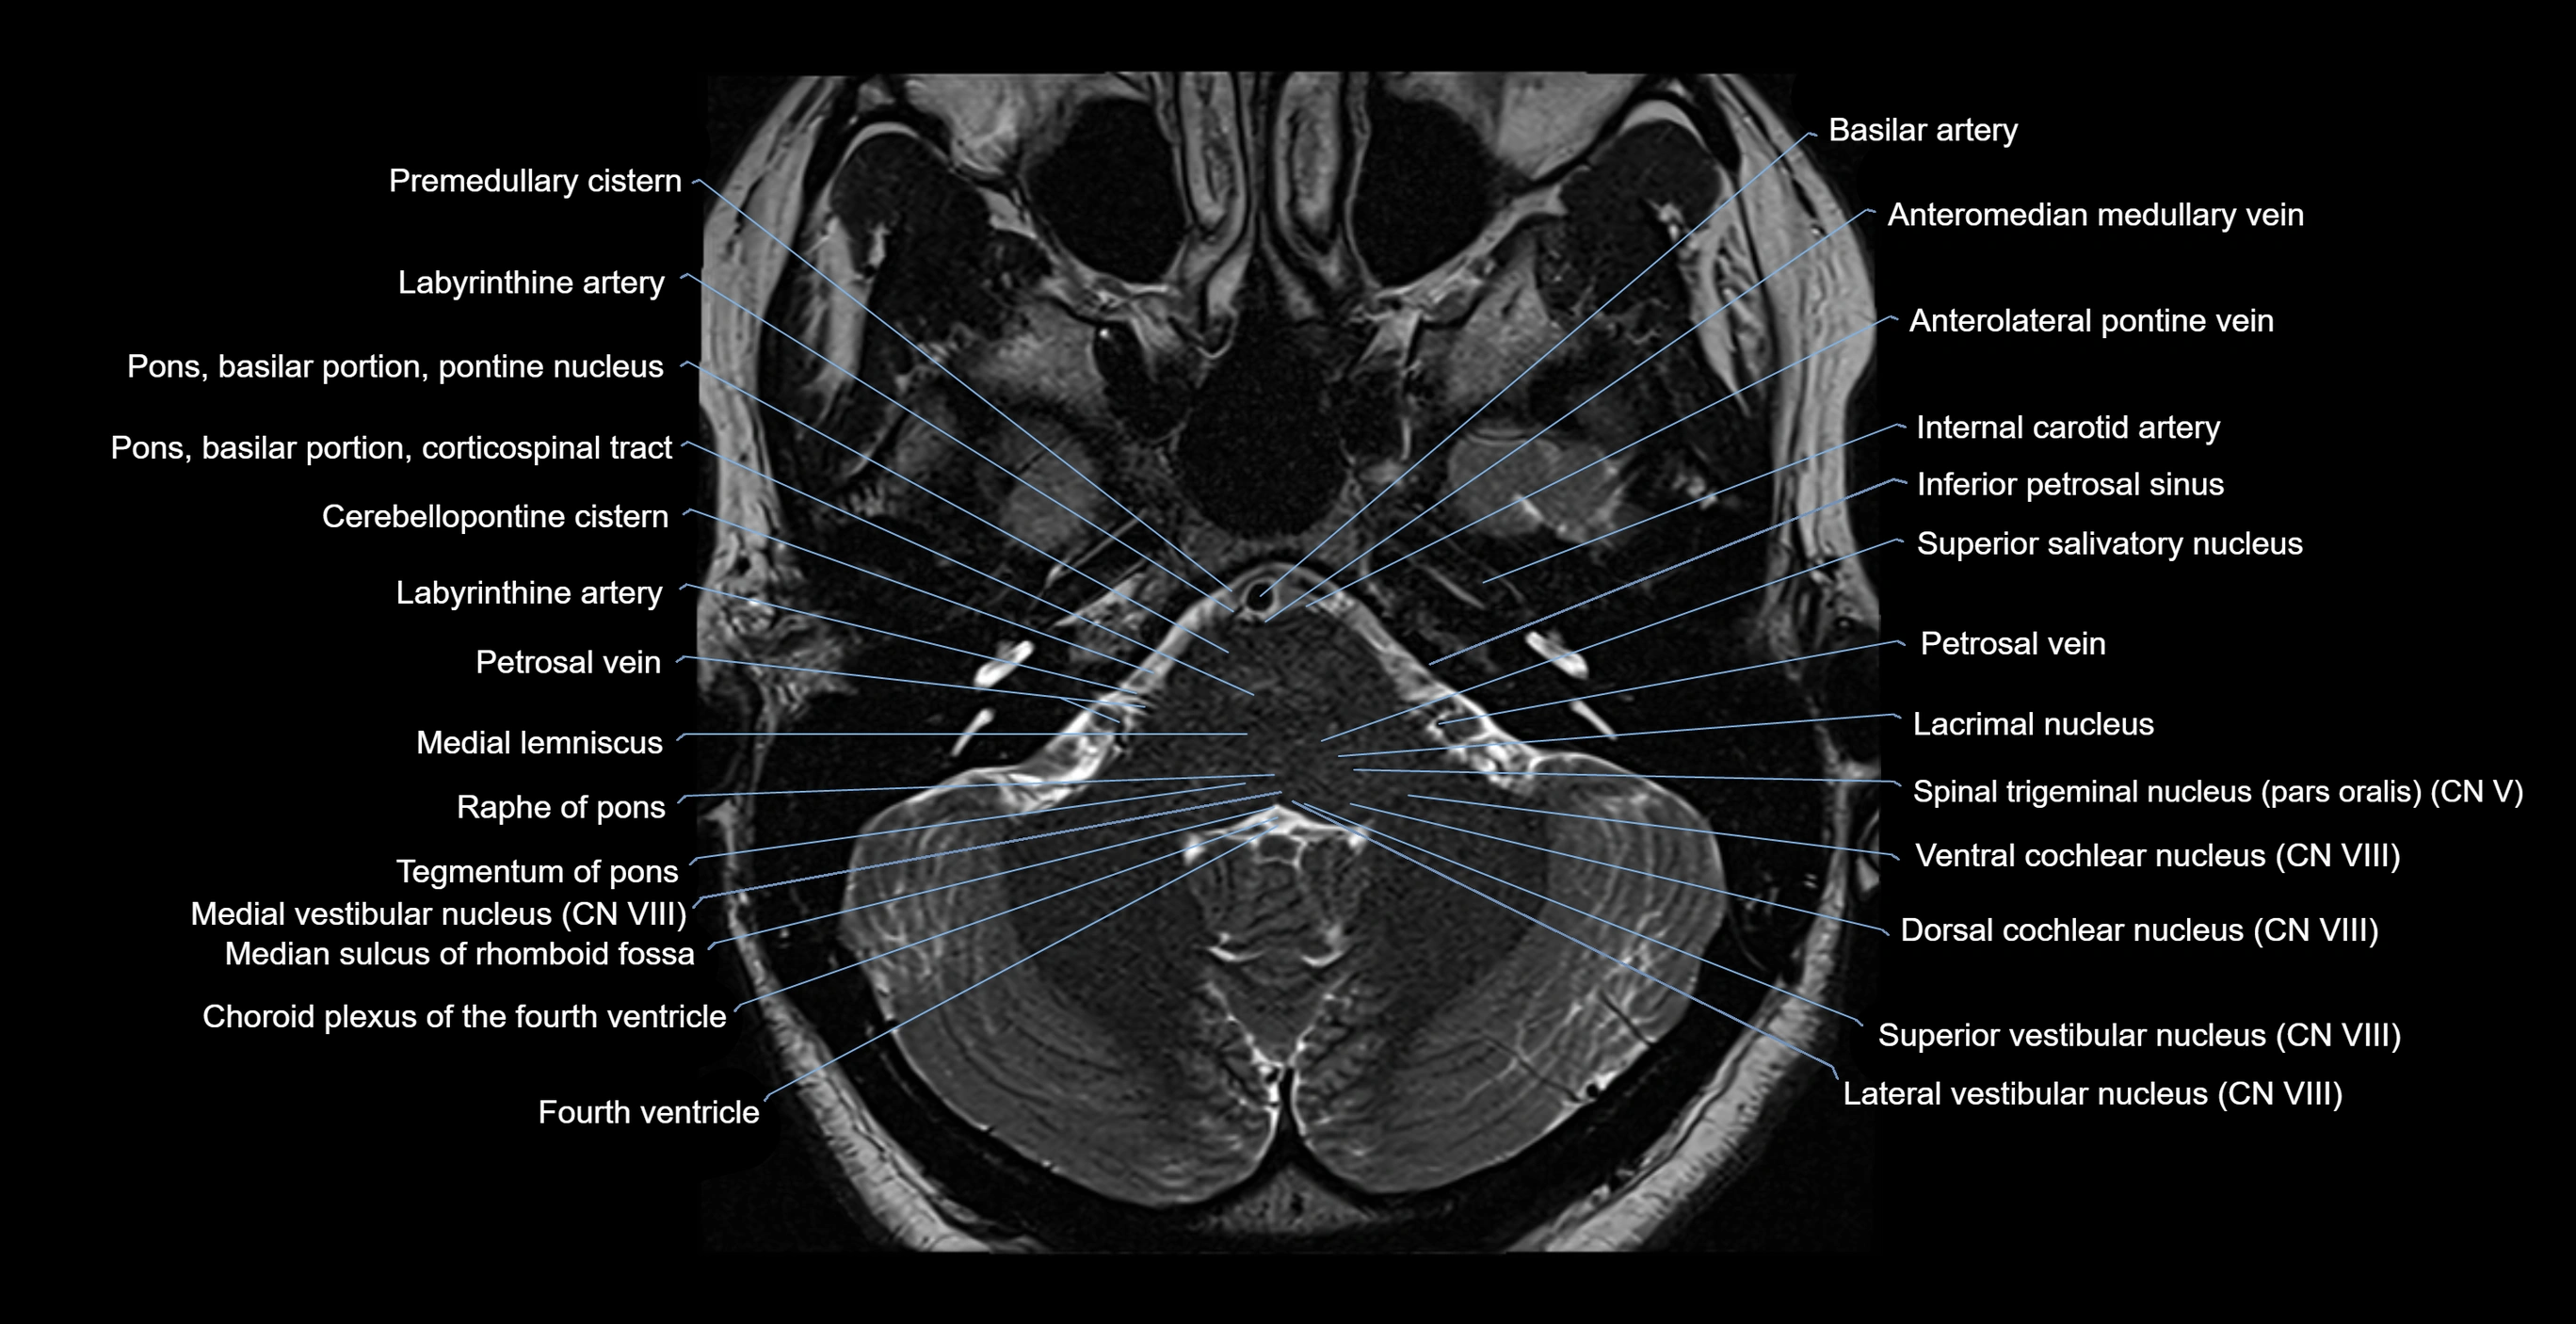

MRI images